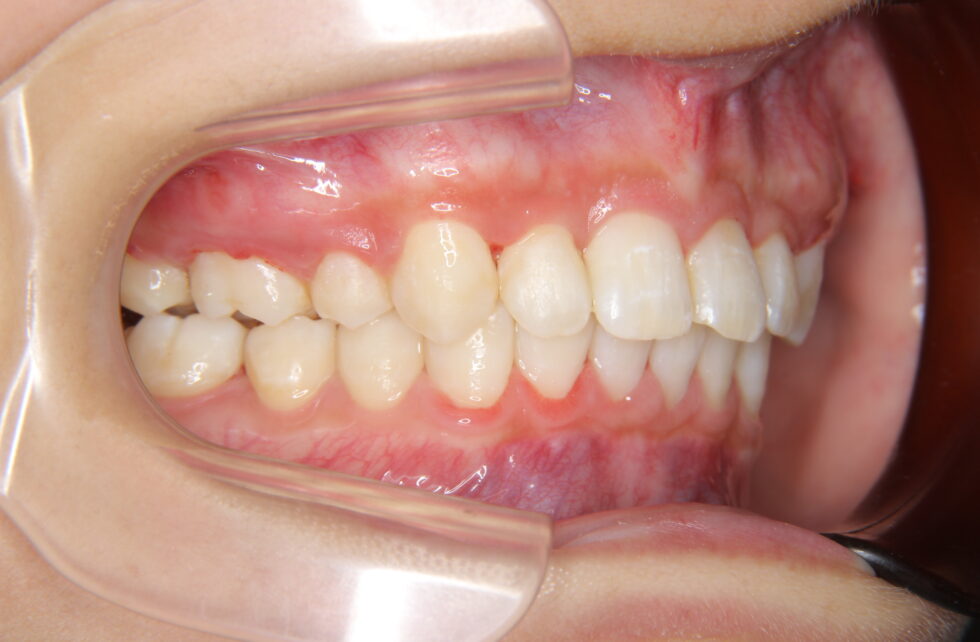

初診時年齢24歳の女性 上顎前歯の内傾を主訴にご来院いただいた。長年、前歯が内側を向いていることを気にされていたが治療を行う勇気が出なかったとのことであった。しかし、咬合時に上顎前歯に痛みを感じるようになったことから治療を希望された。セファログラム他の分析から咬合力の極めて強いと考えられる骨格をされていることが分かった。上あごの前歯が内側を向いた骨格性上顎前突で、アングルの分類Ⅱ級2類と診断した。咬合力が強いと歯の動きは緩徐で、前歯のかみ合わせが深くなり、上あごの前歯の後退が困難になる場合がある。このため、上顎左右側小臼歯を抜歯していただき、矯正用アンカープレートを併用して、上下顎マルチブラケット装置を使用して動的治療を行った。内側を向いていた上顎前歯は適正な角度とすることができた。

矯正を始めてから長い時間がかかりましたが、今ではきれいな歯並びになり、歯の痛みもなくなり本当に良かったです。